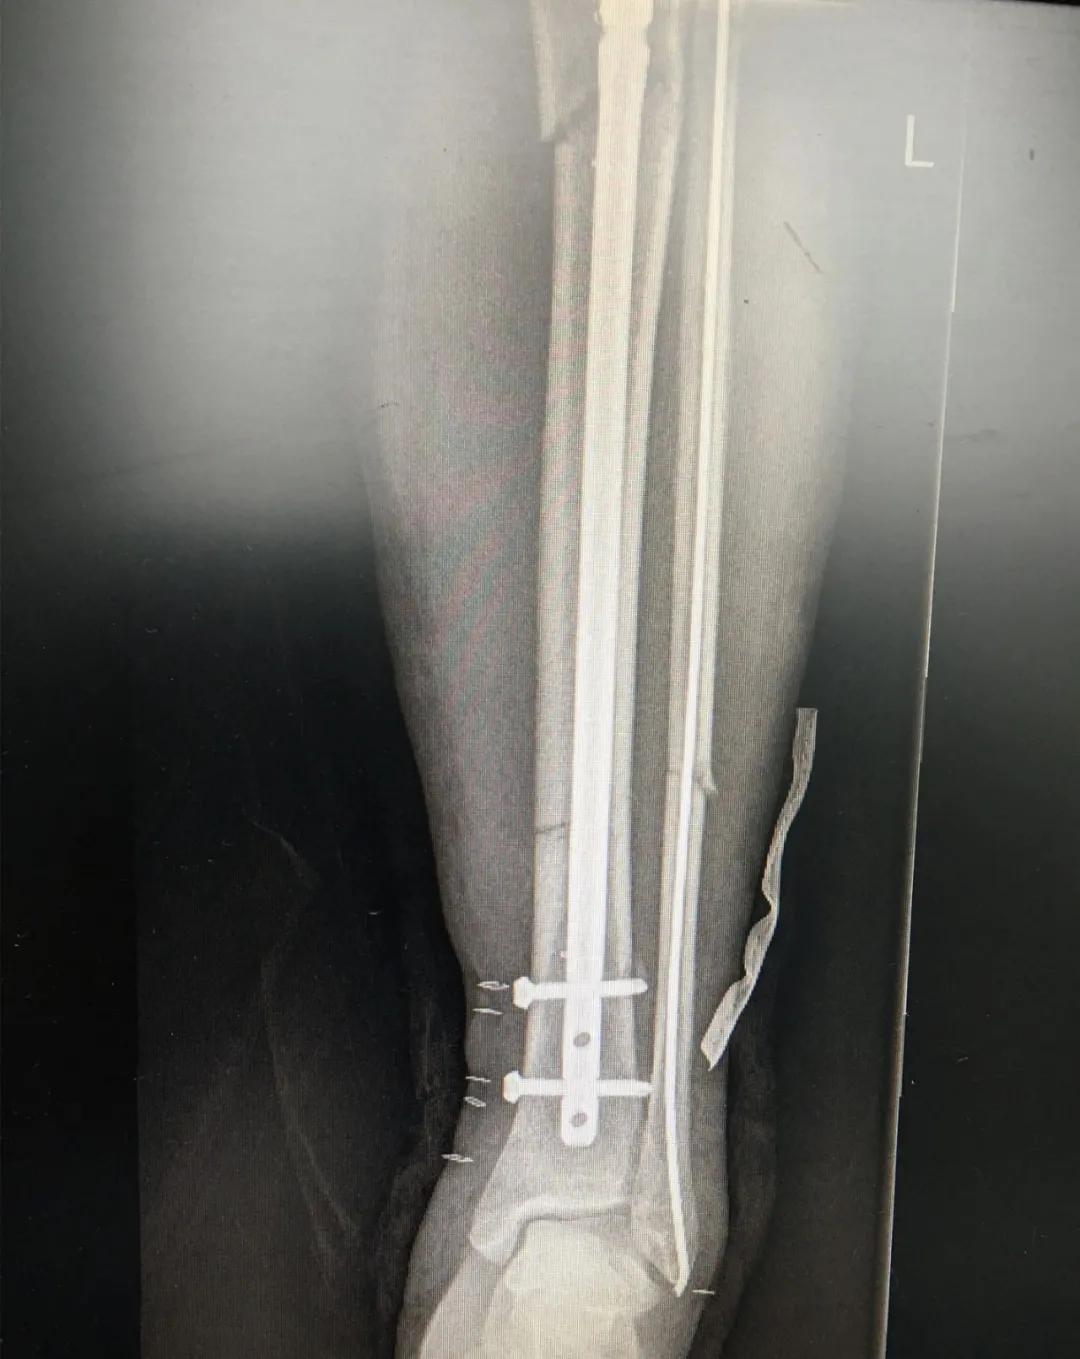

为患者实施的骨折微创复位固定技术是创伤骨科的特色技术。相较传统手术需要20公分的切口,微创手术只需要3公分左右。闭合复位髓内钉固定技术、经皮插板内固定技术(mippo技术)、闭合复位空心螺钉固定技术等一系列的微创复位固定技术,具有切口小、出血少、创伤小、愈合快、疤痕小等优点,骨折术后并发症明显降低,患者还可以早期负重功能锻炼。

另一位患者朱先生因车祸导致了右胫腓骨骨折,同样的小腿三段骨折,实施了微创闭合复位髓内钉固定术后,目前已经逐步进行康复功能锻炼。